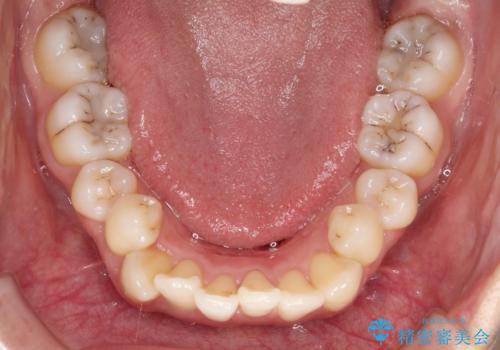

前歯が前後反対にかんでいる インビザラインによる目立たない矯正

- 前歯のかみ合わせを主訴に来院されました。

歯と歯の間をわずかに削り、ガタガタを改善しました。

目立たずに矯正を終えることができて、喜んでいただけました。